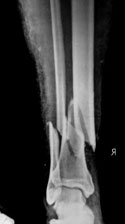

• Nonunion

- Proximal Tibia

- Tibia